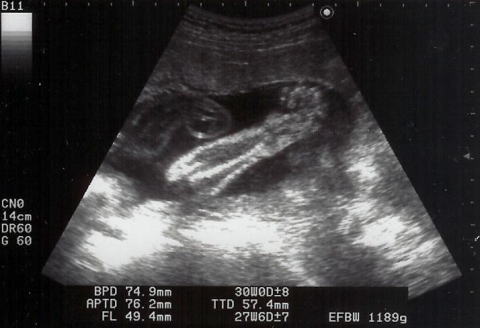

|  |  shigeru26週の健診です。shgieruは841gになりました。心音もしっかりしていて、元気・順調です。ママも今回は体重OK。でも、「塩分は控えめ」(高血圧気味)

と母子手帳に書かれてしまいました。